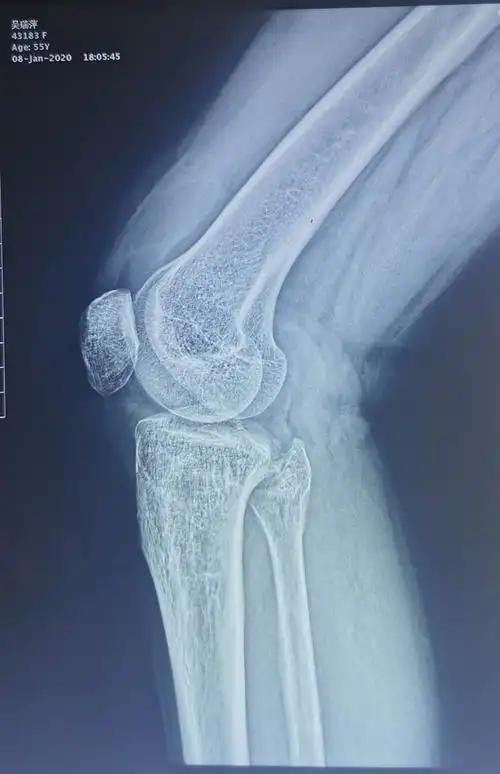

胫骨平台后外侧骨折腓骨头上入路内固定一例

胫骨外侧髁